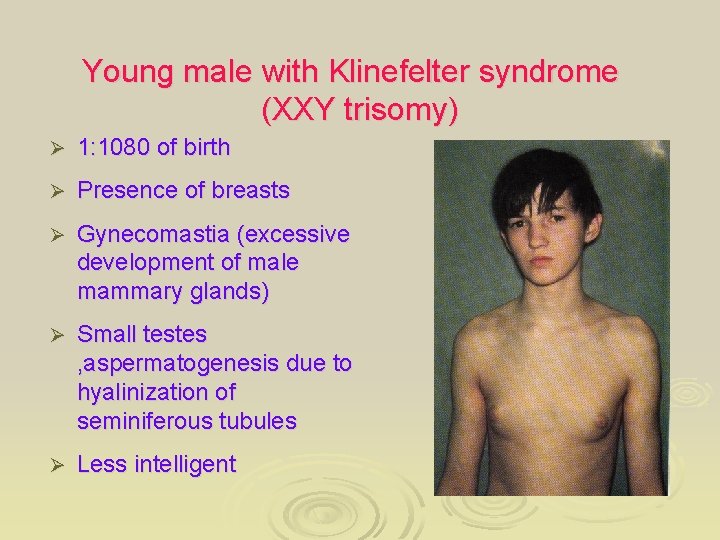

Young male with Klinefelter syndrome (XXY trisomy) Ø 1: 1080 of birth Ø Presence of breasts Ø Gynecomastia (excessive development of male mammary glands) Ø Small testes , aspermatogenesis due to hyalinization of seminiferous tubules Ø Less intelligent